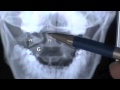

ANATOMY 2.0: INTERPRETATION OF SPINE X-RAY STUDIES

By

cuneatos

74K views

14 years ago